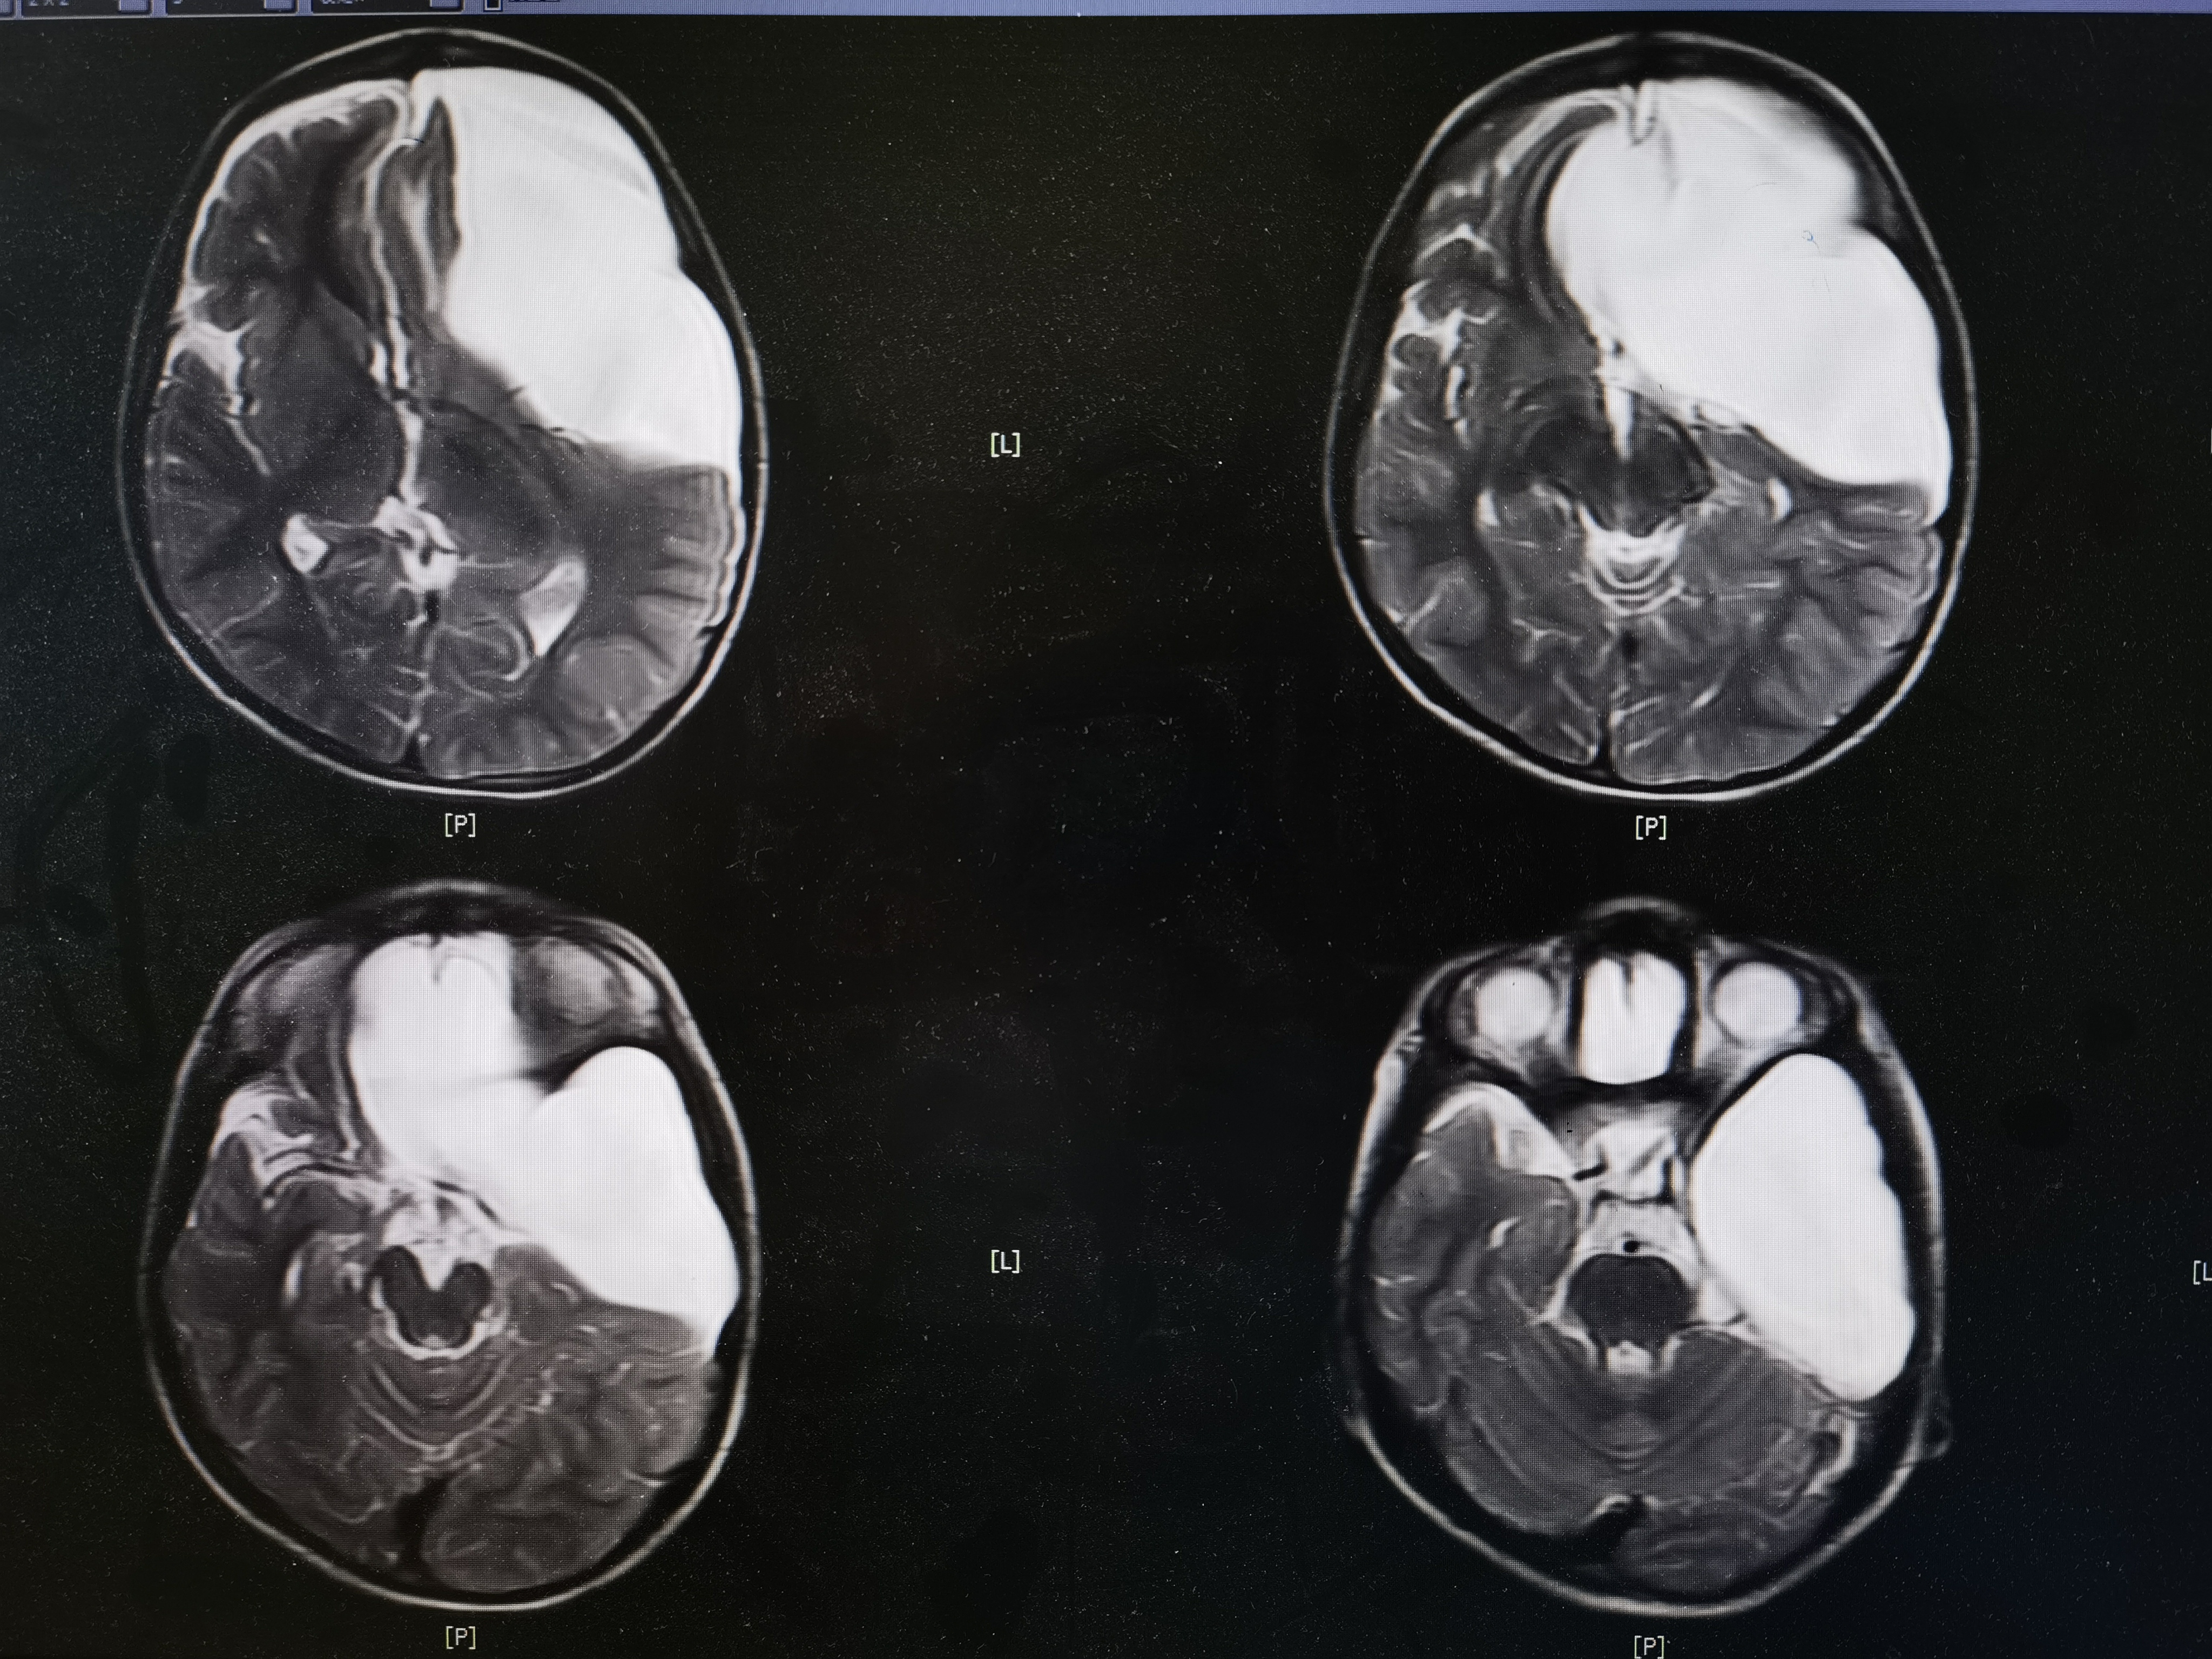

8岁男孩,以“头部外伤后头晕8天”入院,患儿8天前于3米高处坠落摔伤头部,伤后有昏迷史,当地医院CT提示左额颞巨大蛛网膜囊肿,破裂可能。患儿伤后感头晕,当地医院建议转至我院。我院完善头颅MR提示左额颞巨大蛛网膜囊肿,局部越过中线突入右侧镰旁挤压右额叶,左侧额颞岛叶明显受压,囊肿破裂可能。

术前MR